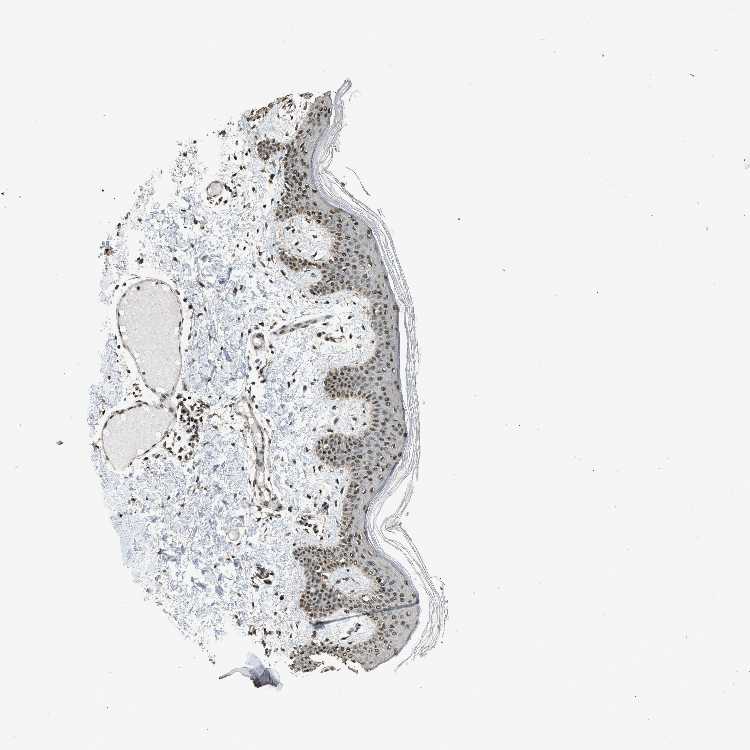

SKIN 2 - Antibody stainingi

Antibody staining in the annotated cell types in the current human tissue is reported as not detected, low, medium, or high, based on conventional immunohistochemistry profiling in selected tissues. This score is based on the combination of the staining intensity and fraction of stained cells.

Each image is clickable and will lead to virtual microscopy that enables deeper exploration of all samples and also displays staining intensity scores, fraction scores and subcellular localization as well as patient and tissue information for each sample.

Antibody CAB017704

Epidermal cells Medium